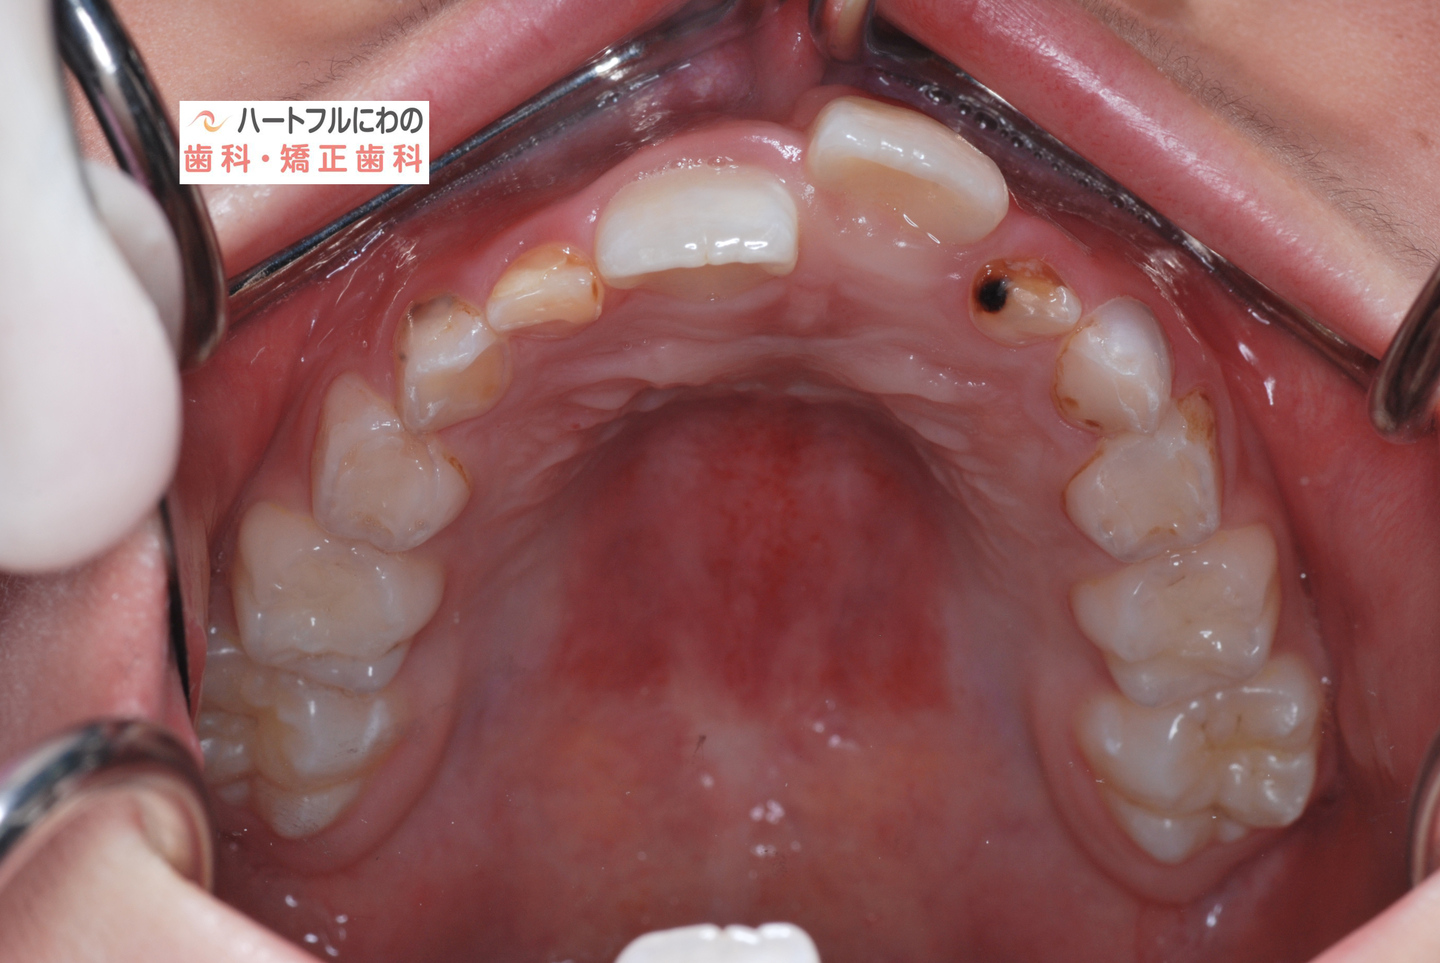

お口の中を拝見すると、上下の叢生(いわゆるガタガタ、乱ぐい)がみられ、多数の虫歯と歯肉炎がみられました。上唇小帯(上唇のすじ)の問題もありました。口呼吸で口腔内が乾燥すると通常の何倍も歯垢が付きやすくなり、虫歯や歯肉炎が頻発します。口呼吸の強い子は重なっている部分のかみ合わせが深い(下の歯がほとんどみえない)のもよく見られる特徴です。

約半年間、成長不全の顎骨を正常に整え、歯の移動も並行して行いました。治療開始から口呼吸の問題は約2か月で大幅に改善、3か月で夜間睡眠は改善し夜尿もほぼなくなりました。それに伴って徐々に他の問題も改善されていきました。小帯に対する外科処置も含めて当院で行うことができます。

治療開始から約6か月後に固定式の装置(患者さんが自分で取り外しできない装置)から、呼吸や筋機能の改善を主な目的とする可撤式の装置(取り外しできる装置)に変更し、正常な呼吸と筋機能を獲得するためのトレーニングを行いながら、全ての永久歯が萌出して仕上げの矯正に移行するまで待ちます。